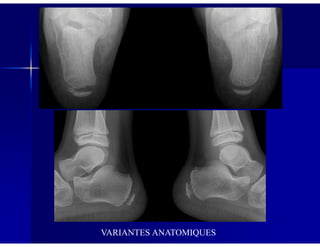

Patient asymptomatique : aspect petit et condensé du naviculaire (variante

anatomique)

* RX effectuées pour traumatisme de la cheville